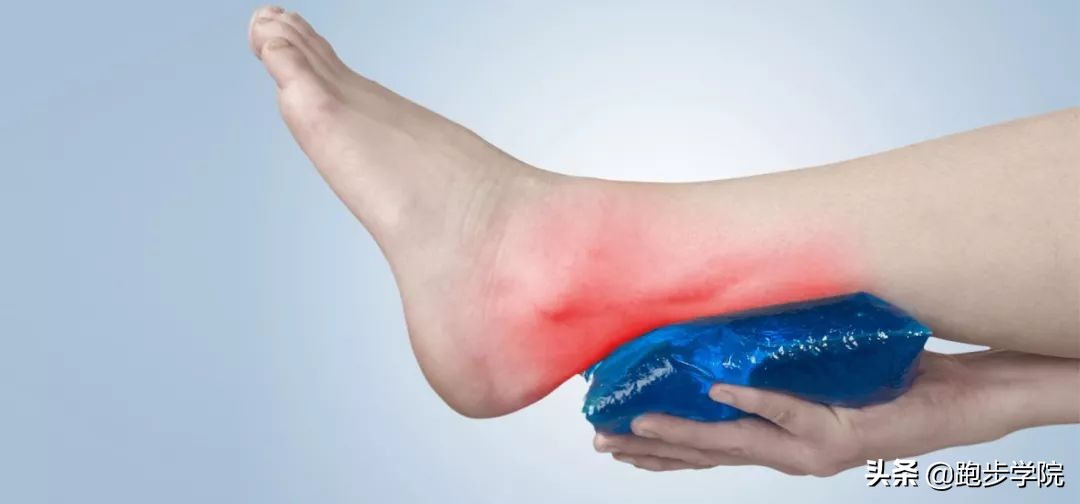

▇ 冰敷

在跟腱炎急性期时,运动者通常会出现明显的肿胀以及疼痛。所以第一件要做的就是停止训练,避免二次损伤。随后使用冰水混合物对跟腱进行冰敷,以控制肿胀,但要注意每次冰敷不要超过 20 分钟,避免对皮肤造成损伤。